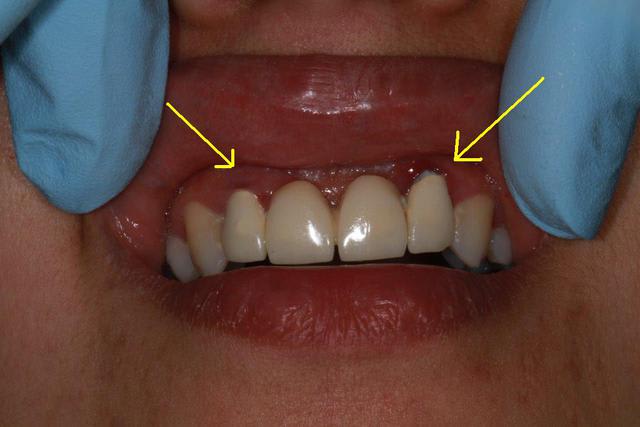

Patiente sympa, 30 ans, un bridge ceramo-métal fait il y a 10 ans, en fin de vie.

Les endo et les IC dans les 12-22 sont sublimes...et ça a durer 10 ans....incroyable...Il y a pas de la paro aussi ?

Oui et un peu particulier au niveau de 12/22, le bridge a été fait suite à un accident sur 11/21, mais soit l'accident était grave, soit le confrère Marocain, un peu pressé.